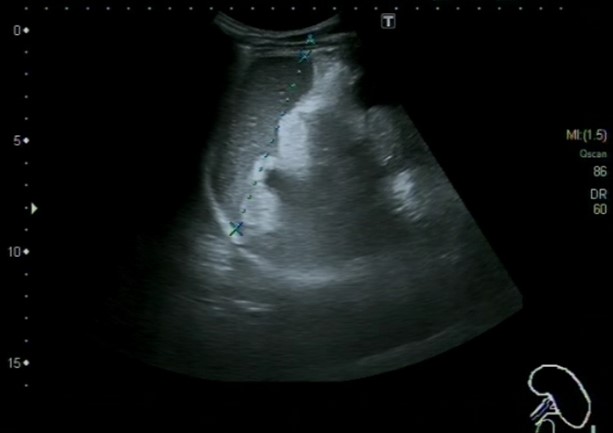

Hallazgos ecográficos

Ascitis a estudio, sugestiva de peritonitis tuberculosa

La ecografía clínica es una herramienta esencial en el diagnóstico de la ascitis. Permite la identificación y cuantificación precisa del líquido, además de evaluar su distribución. La realización de paracentesis guiada por ecografía es fundamental para establecer la causa subyacente de la ascitis, permitiendo obtener muestras de líquido para su análisis. La combinación de la ecografía y la paracentesis mejora la precisión diagnóstica y guía la atención médica apropiada.